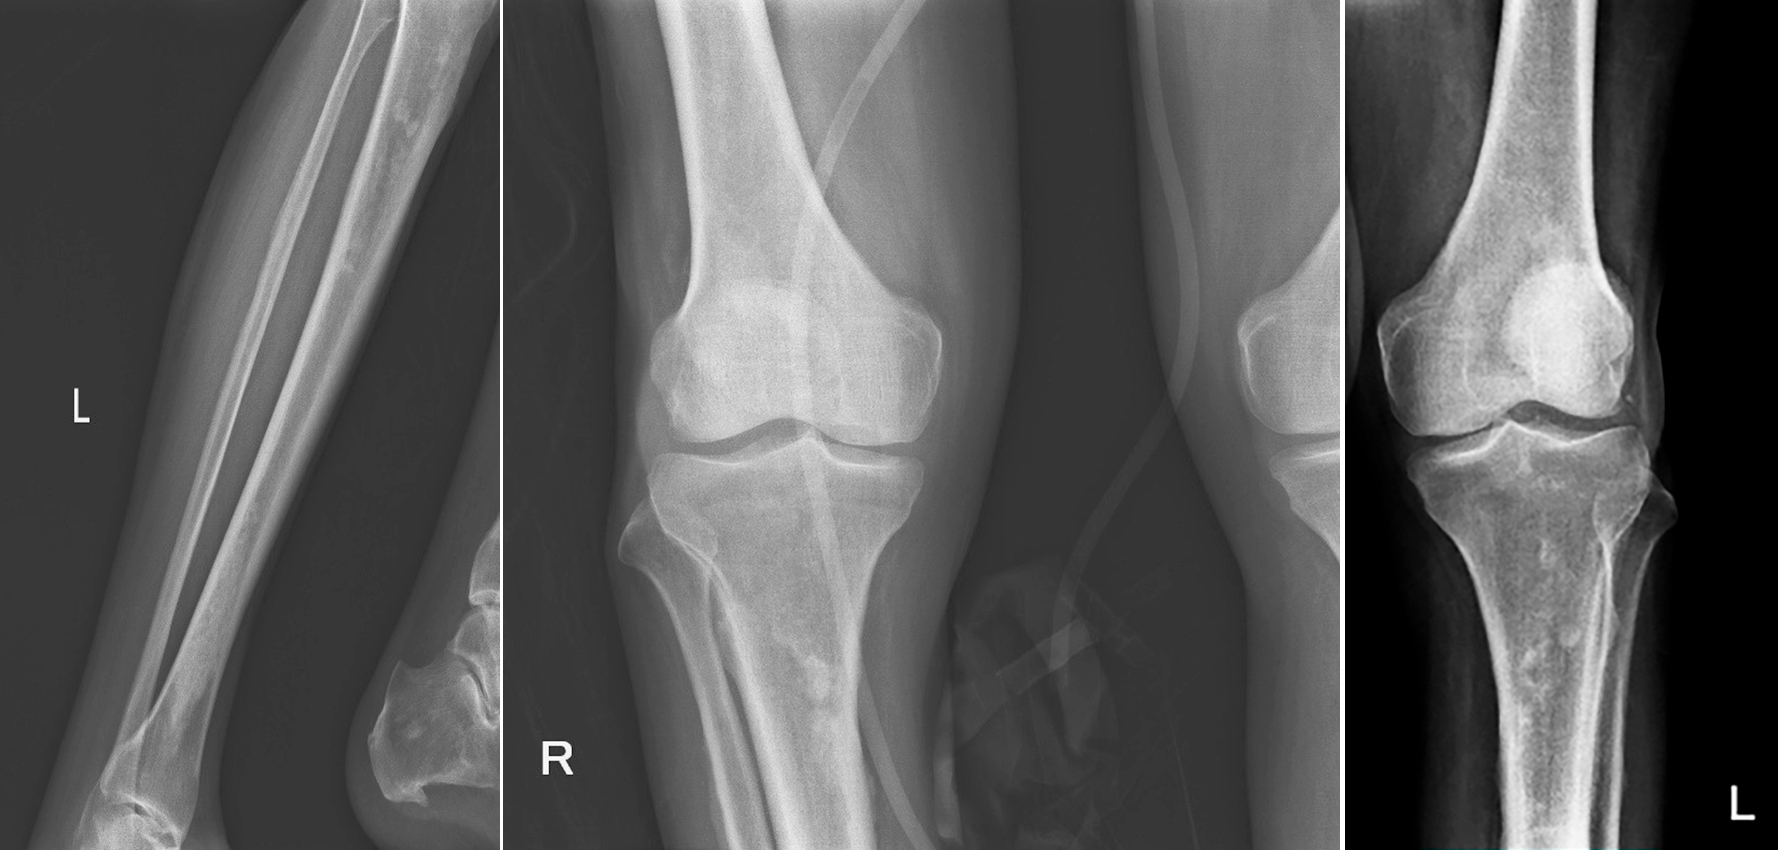

Для подтверждения данного предположения пациенту выполнена рентгенография трубчатых костей: выявлен островковый метафизарный и диафизарный склероз, в большей степени выраженный в большеберцовых костях (рисунок 3) — патогномоничный признак БЭЧ.

Рис. 3. Поражение костей

Нелангергансоклеточный гистиоцитоз (синдром Эрдгейма-Честера) с поражением трубчатых костей (метафизарный и диафизарный склероз трубчатых костей голеней), поражением кожи (ксантомы), поражением сердца и артерий (периваскулярная инфильтрация аорты и ее ветвей, псевдоопухоль предсердия), поражение клетчатки забрюшинного пространства, средостения, брюшной полости, поражением почек, ЦВС.